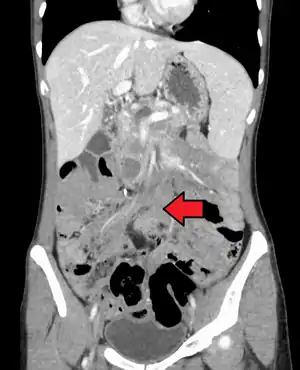

![]() | |

| Desmoid tumor as seen on CT scan | |

MRI or CT imaging scans are commonly used for monitoring.[45][1]